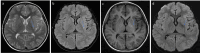

Case presentation: We present the case of an 8-year and 5-month-old boy with basal ganglia lesion who exhibited TWs in the local C3 lead on electroencephalography. Subsequent EEGs revealed no additional abnormalities. During the follow-up at 1 year and 8 months, there was no significant change in the patient's condition.